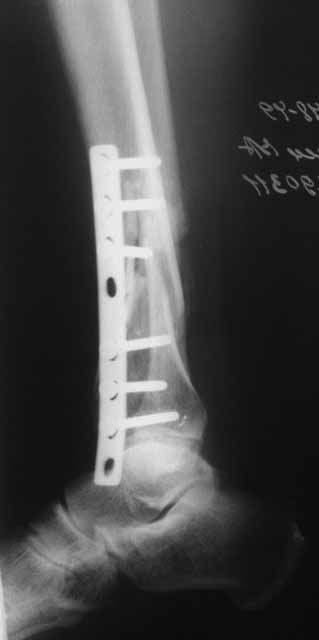

Это гипотрофический ложный сустав. Проблем видится несколько:

1. нарушение трофики в месте перелома.

2. после фиксации в аппарате Илизарова на рентгеногнрамме имеются признаки спицевого остеомиелила. В настоящи момент хотя свищей нет с мая 2011 нет опасно ли фиксировать голень стержнем?

На основании каких признаков Вы решили, что кость мертвая! Имеется гиперпластический ложный сустав, как результат недостаточно стабильной фиксации ан предыдущих этапах лечения. В данном случае необходимо решение следующих вопросов:

Примерная ситуация. Пациент 37 лет. Синтезировали где-то пластинкой. Попал к нам через 2 месяца.

19 апреля убрали через проколы пластину с винтами, пересекли fibula, наложили аппарат.

Немного потянули по оси, убрали вальгус, ротацию. 22 апреля (на 3-е сутки) заштифтовали окончательно. 29 апреля выписали из отделения. На все ушло 10 дней.